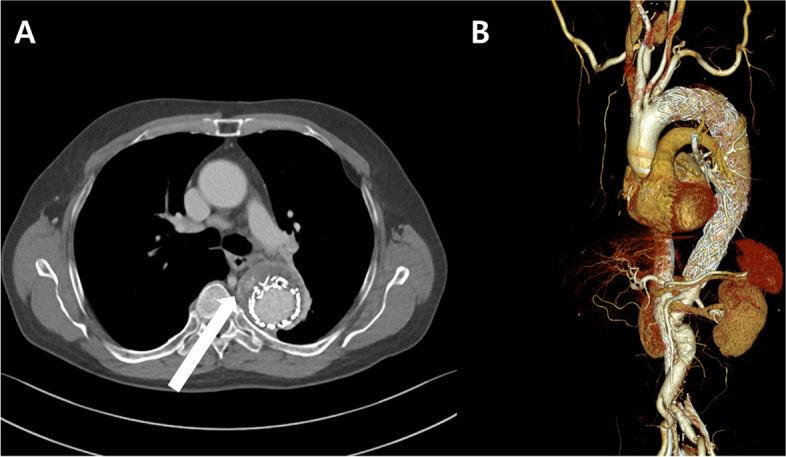

A 62-year-old male patient, previously treated with TEVAR for a descending thoracic aortic aneurysm, presented with ongoing chest discomfort. Based on the diagnosis of a growing aneurysm and type II endoleak, the patient was prepared for CPB and aortic cross-clamping, as a precautions against the possibility of a type I endoleak. A longitudinal opening of the thoracic aortic aneurysm sac was performed following left thoracotomy. Visual confirmation identified the T5 level intercostal artery as the source of the endoleak, and after confirming the absence of a type I endoleak, multiple ligations were applied to the intercostal artery. Follow-up computed tomography confirmed the absence of endoleaks or sac growth.

一名 62 岁男性患者,先前因降主动脉胸主动脉瘤接受 TEVAR 治疗,现出现持续胸痛。根据不断增大的动脉瘤和 II 型内漏的诊断,为预防 I 型内漏的可能性,患者准备接受 CPB 和主动脉阻断。在左开胸手术后,对胸主动脉瘤囊进行了纵向切开。直视下确认 T5 水平肋间动脉为内漏来源,在确认无 I 型内漏后,对肋间动脉进行了多次结扎。随访 CT 证实无内漏或囊腔增大。